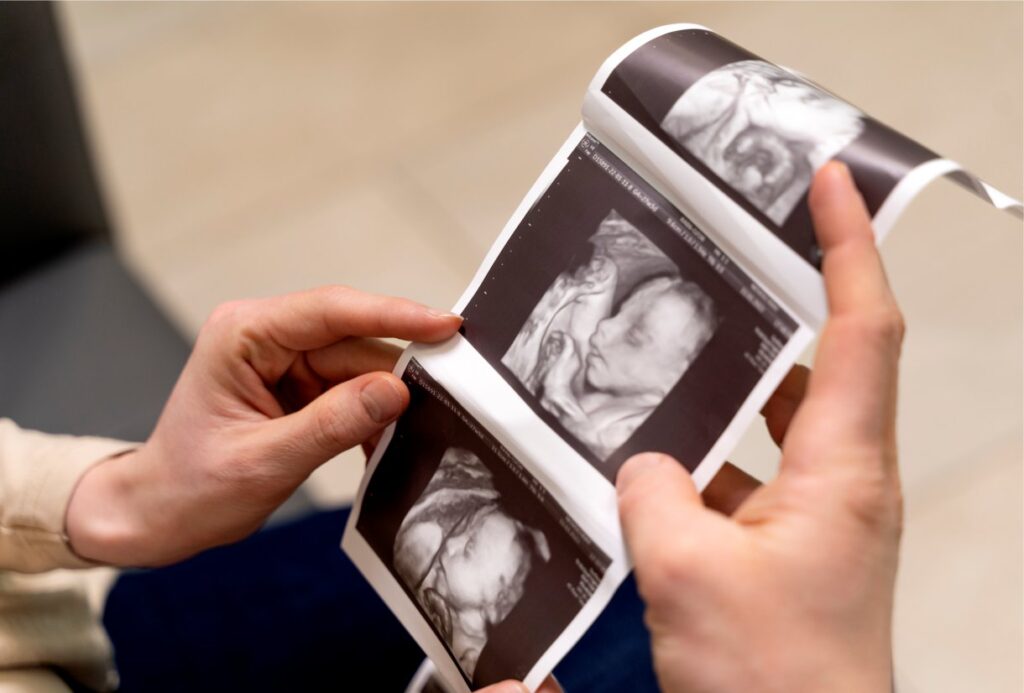

Durante a gravidez, cada detalhe importa. Para as futuras mamães, acompanhar o desenvolvimento do bebê com segurança e tranquilidade é fundamental. E um dos exames mais importantes nesse processo é o ultrassom morfológico.

O ultrassom morfológico é um dos exames mais importantes durante a gestão, pois permite uma avaliação detalhada da formação do bebê e ajuda a detectar possíveis alterações estruturais.